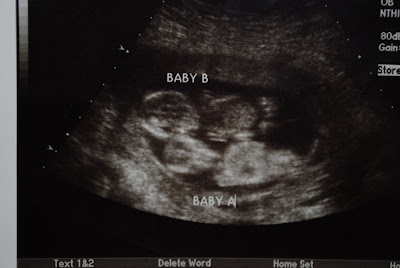

Any way both babies are still breech. Sigh. The doctor checked me and I am at a 1 which doesn't surprise me, I have never dialated on my own to anything larger than a 1. He also informed me that he could feel feet, I know kind of strange huh? So Baby A is definitely breech right now. Next week will be a big appointment. I can't wait to see these guys on ultra sound again and get an estimate on what they weigh and their size.